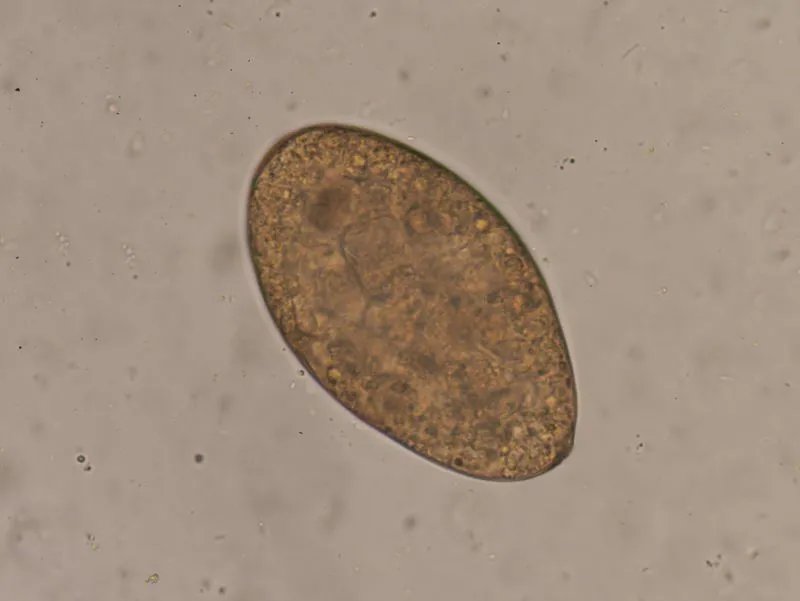

如何预防牛带绦虫在日常生活中多注意个人卫生,保持良好的饮食和卫生习惯,在食用肉类时,必须煮熟煮透,且切生菜和熟菜的厨房用具分开,防止污染。加强对肉类的检验及加工工作,在购买食用肉时,排查食用肉中没有活的囊尾蚴,阻断感染牛带绦虫的感染源。如何检测抽血对血象进行检查,病程早期一般多出现血象变化少,无贫血,嗜酸性粒细胞轻度增多等症状。一般采用直接涂片或厚涂片法进行虫卵检查,大多数患者粪便中可找到虫卵,一般用于普查。由于牛带绦虫与猪带绦虫卵极相似,使用粪便或拭子涂片检查发现的绦虫卵,不能鉴别其虫种。对虫类进行头节检查进行区分,在驱虫治疗后的一天内,留取患者全部粪便,将粪便置大容器中,用清水反复漂洗直至粪液澄清,沉渣转到玻璃容器中,仔细查找头节,牛带绦虫的头节呈近四方形,较大而无顶突与小钩,表明治疗彻底,如有多虫感染可能时应注意链体条数与头节数是否一致。